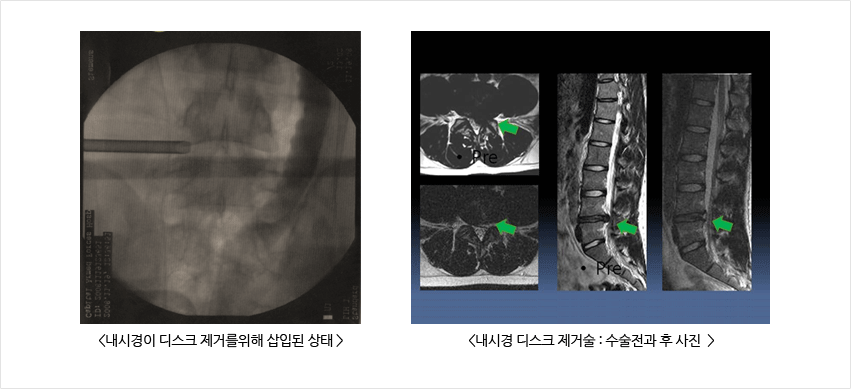

허리디스크 치료 두 번째는 외과적 치료입니다.

몇 가지 수술적 치료법이 있습니다. 복부 절개를 제거하기 위해 신경을 누르는 리본을 제거하는 수술이 있습니다. 허리를 잡은 상태에서 척추를 떼어내는 척추융합술도 있습니다. 마지막으로 레이저로 디스크를 제거하는 레이저 절제술이 있습니다.

척추 수술을 받은 사람들은 환자의 50% 정도가 완치됩니다. 그러나 나머지 50%는 크게 개선되지 못했습니다. 따라서 병원에서 허리 디스크의 작동을 마지막 진단 수단으로 고려해야 합니다.